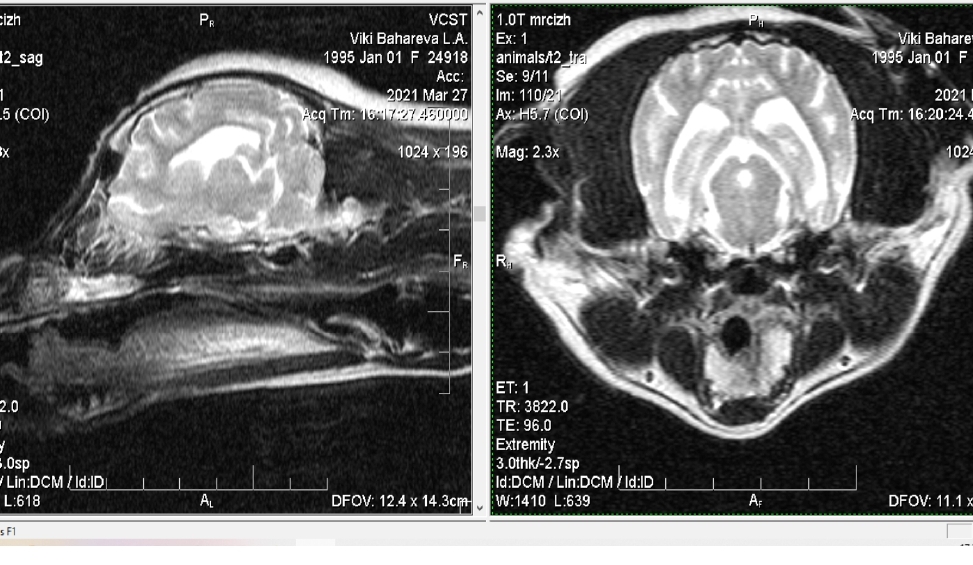

Прежде всего, необходимо произвести специальную диагностику. Рентгеновское исследование неспособно дать все необходимые сведения, как правило, требуется проанализировать результаты компьютерной и магнитно-резонансной томографии, обычно использующиеся в ветеринарной неврологии и отличающиеся более высокой точностью.